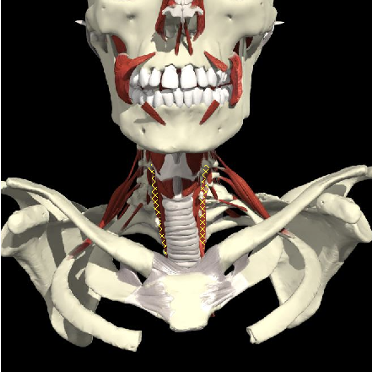

Contralateral Rotation

Anatomy

- SCM

- Scalenus anterior

- Semispinalis capitis

- Semispinalis cervicis

- Spinalis cervicis

Ipsilateral Rotation

- Splenius capitis

- Splenius cervicis

- Longissimus capitis

- Sub-occipital